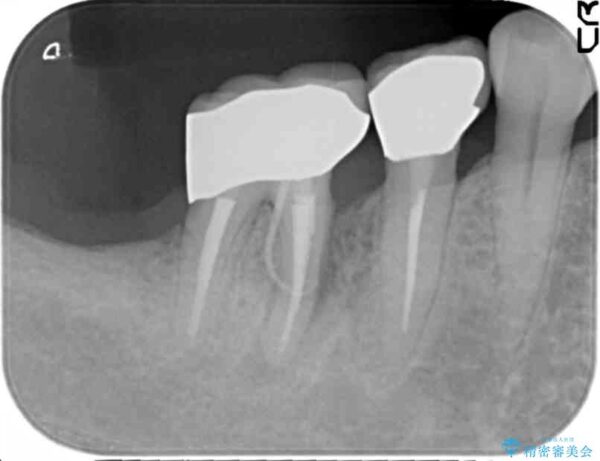

精査した結果、奥歯の根は破折しており抜歯を避けられない状況でした。

咬合力が強く、その他の歯の破折も防ぐために奥歯の咬合機能をインプラントを用いて回復する治療計画を立てます。

治療前

奥歯から膿のにおいがする インプラントによる機能回復 治療前画像 奥歯から膿のにおいがする インプラントによる機能回復 治療前画像 奥歯から膿のにおいがする インプラントによる機能回復 治療前画像 奥歯から膿のにおいがする インプラントによる機能回復 治療前画像 奥歯から膿のにおいがする インプラントによる機能回復 治療前画像 奥歯から膿のにおいがする インプラントによる機能回復 治療前画像

治療中

奥歯から膿のにおいがする インプラントによる機能回復 治療中画像 奥歯から膿のにおいがする インプラントによる機能回復 治療中画像 奥歯から膿のにおいがする インプラントによる機能回復 治療中画像 奥歯から膿のにおいがする インプラントによる機能回復 治療中画像